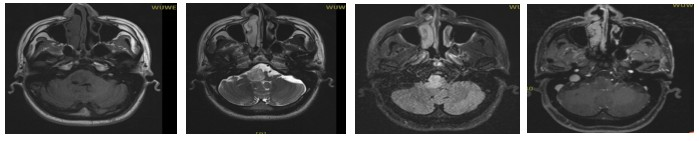

Pre-treatment MRI: A space-occupying lesion in the right part of the brainstem, measuring 2.2 × 2.0 cm, with compression of the adjacent fourth ventricle, highly suggestive of glioma.

- GTV (Gross Tumor Volume): The visible medullary lesion on MR T2 flair imaging.

- CTV (Clinical Target Volume): GTV with a 1.5 cm margin.